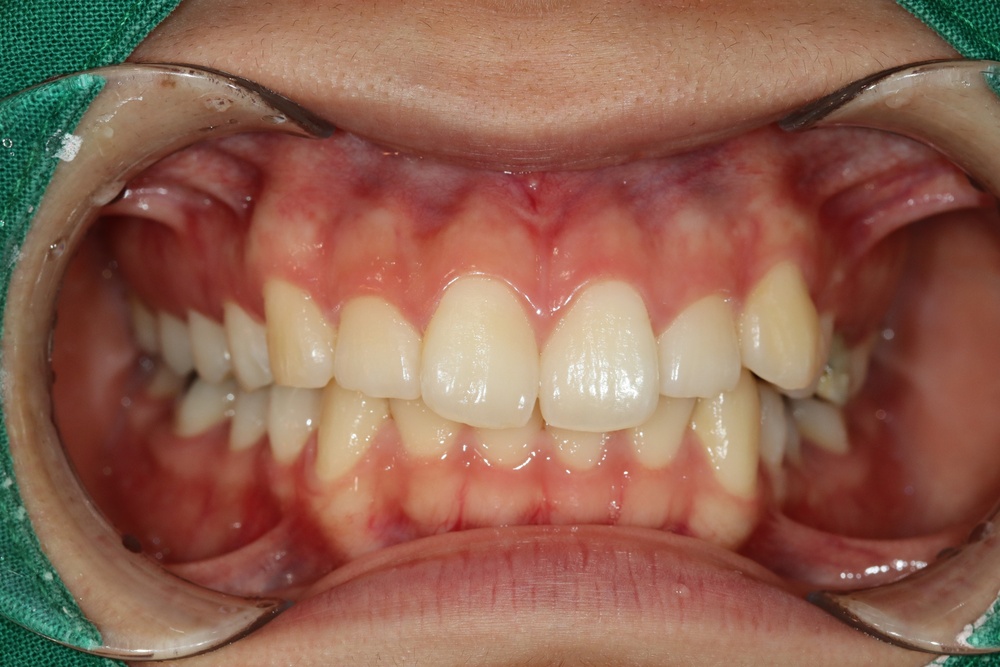

교정 후 왜소치를 레진수복했는데, 벌어지고 변색이 심해서 내원하셨습니다.

벌어진 공간을 교정으로 닫는것보다는 보철로 치아 크기를 키우는 것이 비용과 심미 면에서 유리해 보여서 추천드렷습니다.

치아의 최소삭제 후 라미네이트를 붙인 모습입니다.

보철물 부착을 위해 교정 유지철사도 제거 후 재제작하였습니다.